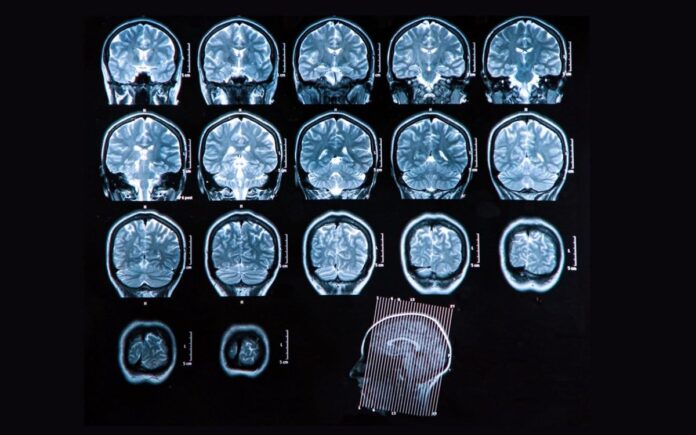

ΣΚΛΗΡΥΝΣΗ ΚΑΤΑ ΠΛΑΚΑΣ